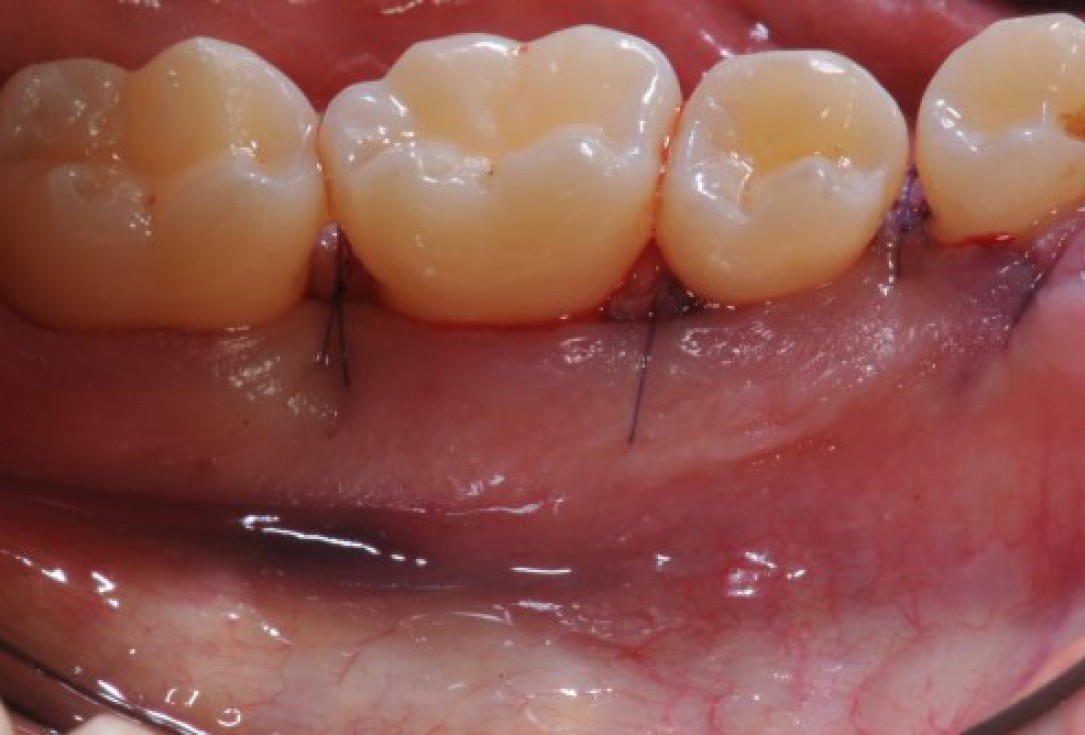

01/22 - Pre-surgical clinical situation, buccal view.

Deep intrabony defects treated using Straumann® Emdogain® - Dr. M. Stefanini